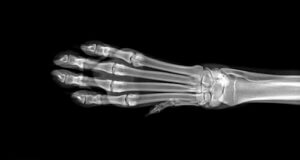

Wenn du deinen Hund zu einem Tierarzt bringst, weil er geschwollene Beine hat, dann wird dieser zuerst einige diagnostische Tests vornehmen, um die Ursache zu identifizieren. Dazu gehören Blut- und Urinuntersuchungen und häufig auch Röntgenuntersuchungen der betroffenen Gliedmaßen.

Falls diese Untersuchungen noch keine eindeutigen Ergebnisse liefern, kann auch ein MRT erforderlich werden. Wenn der Tierarzt ein Osteosarkom vermutet, wird er außerdem eine Knochenbiopsie durchführen.